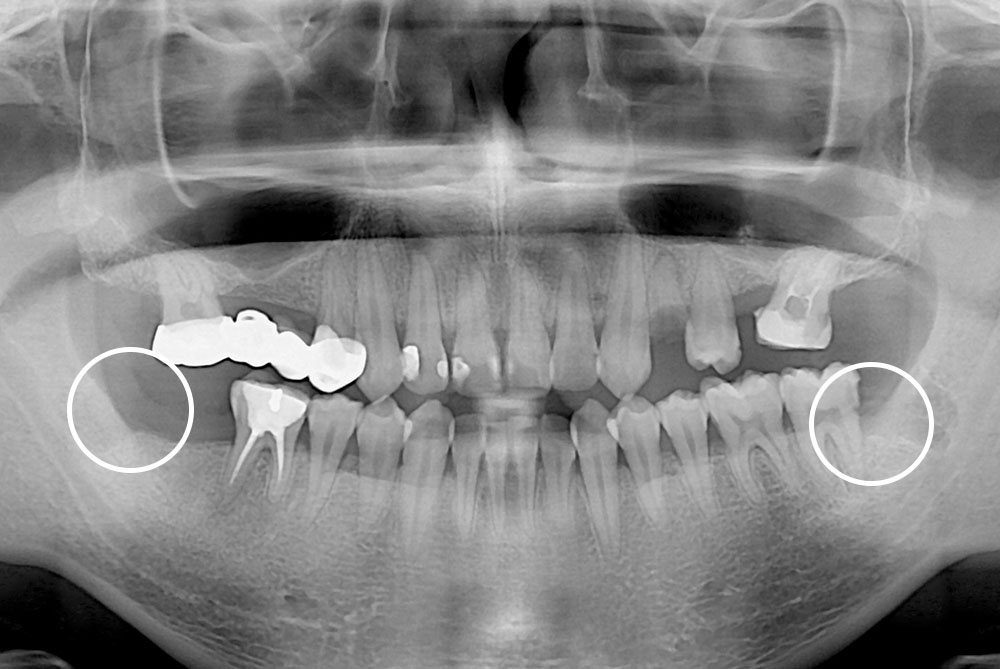

치료사례

세종치과의 진심 어린 치료는 결과로 말합니다.

실제 내원하신 환자분들의 치료 전·후 사례를 확인해보세요.

모든 치료사례 전후사진은 환자분의 동의하에 촬영되었습니다.

모든사진은 동일 환자분의 전후모습을 촬영하였으며, 사진의 밝기조절 외에 임의 수정이 없음을 알려드립니다.